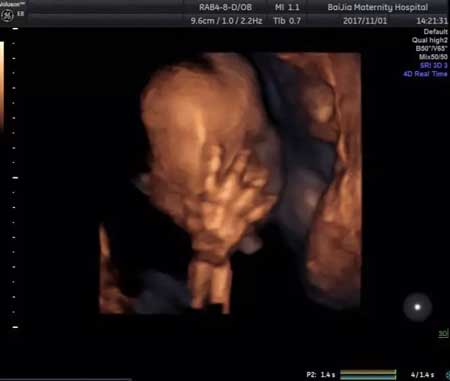

上面这些,都是在中孕期的超声影像筛查时看到的哦~

中孕期的超声影像,除了让宝妈们看到胎宝宝在宫内的表情,它更重要的一个任务是:对胎宝宝的结构畸形进行筛查!